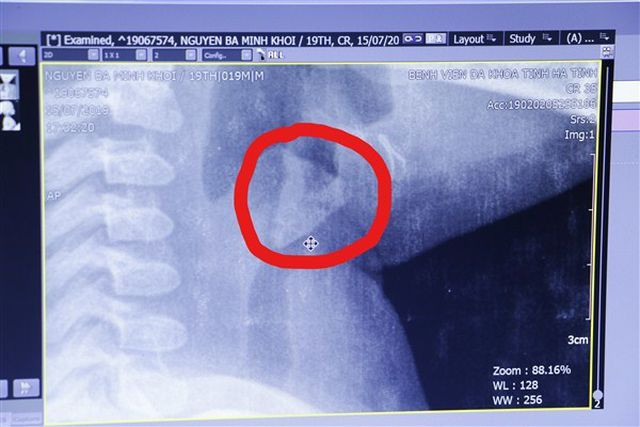

Hình ảnh di vật trong thanh quản cháu Nguyễn Bá Minh Khôi.

Sau khi làm các xét nghiệm cần thiết cộng với chụp X-quang, các bác sỹ phát hiện hình ảnh cản quang bất thường ở khí quản.

Ngay sau đó, các bác sỹ Khoa Khoa Tai - Mũi - Họng thực hiện gây mê nội soi lấy được mảnh xương hình tam giác với kích thước 1,5x1,2x0,2cm ở thanh quản.